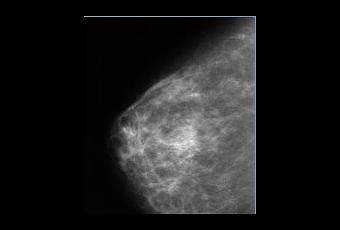

Un test génétique pourrait permettre de prédire le cancer du sein, des années à l'avance, en détectant, à la surface d'un gène spécifique, une modification de l'ADN appelé méthylation, causée par l'exposition à des facteurs environnementaux tels que les hormones, le rayonnement, l'alcool, le tabagisme et la pollution. Ce niveau de méthylation pourrait être un biomarqueur de risque de cancer, en particulier chez les femmes de moins de 60 ans. Ces données préliminaires au développement d'un test sanguin de détection du risque, viennent d'être publiées dans l'édition de mai de la revue Cancer Research.

Les chercheurs ont utilisé les résultats de 3 études cohorte qui avaient prélevé des échantillons sanguins provenant de plus de 600.000 femmes sans cancer au départ de l'étude. 640 de ces femmes ont développé un cancer du sein. En plus des échantillons de sang, des informations ont été recueillies sur les autres facteurs de risque de cancer du sein tels que des facteurs hormonaux et de la reproduction, le tabagisme ou la consommation d'alcool. Les chercheurs ont analysé les échantillons de sang afin de déterminer le degré de méthylation au sein d'un gène spécifique appelé le gène ATM, un gène impliqué dans de nombreuses fonctions, dont la division cellulaire et la réparation de l'ADN, puis ont comparé le niveau moyen de la méthylation entre les cas de cancer et les témoins sains afin de déterminer s'il y avait une différence significative dans le degré de modification du gène ATM. Les participantes ont été réparties en 5 groupes en fonction de leur niveau de méthylation. Pour chaque groupe, les chercheurs ont évalué le risque de cancer du sein.